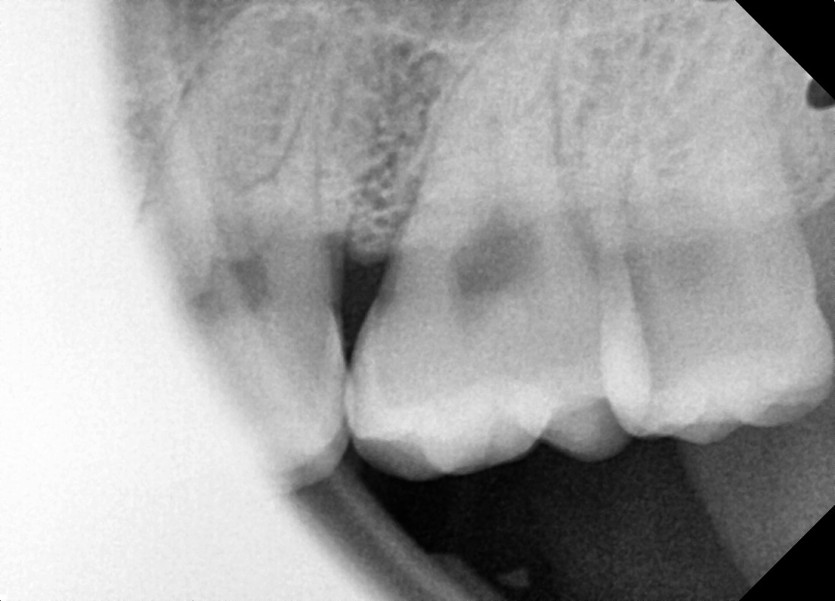

#28,38 사랑니 발치

구강 외과 전문의가 당일 발치했습니다.